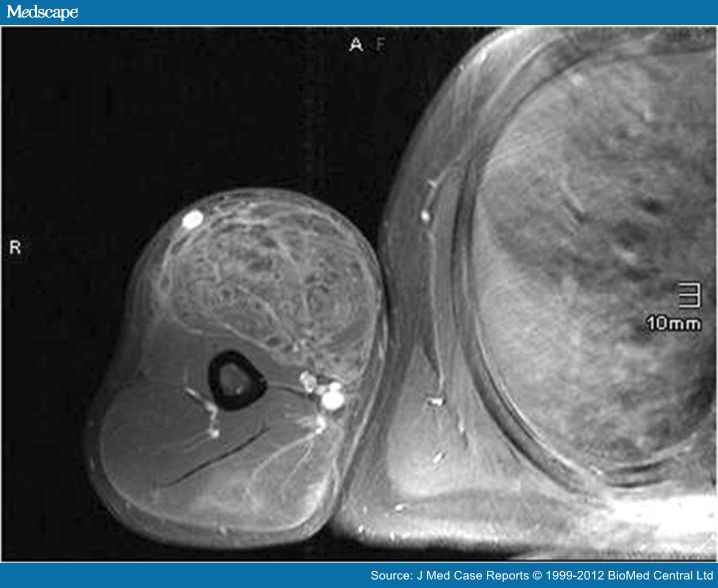

From www.medscape.com

Muscle Fibrosis Following Synthol Injections in a Bodybuilder Oil Injection Muscle Infection He described numerous intramuscular injections of site enhancement oil,. Synthol is a site enhancement oil used by bodybuilders to boost the cosmetic appearance of muscles. Physical discomfort and pain are immediate reactions to synthol injections. Users may experience redness, swelling, and inflammation at the injection site. More alarmingly, there’s a risk of. 3 heart & vascular center, brigham and women's. Oil Injection Muscle Infection.